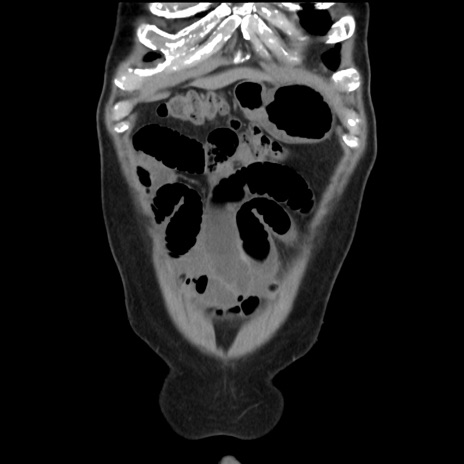

症例16(冠状断像)

【症例】 70歳代男性

【主訴】 腹痛、嘔吐

【現病歴】 約1ヶ月前より間欠的に腹痛と嘔吐あり、当院消化器内科を受診したところCTで多発する肝臓のLDAを指摘され、精査中であった。以降は消化器症状は安定していたが、2日前より嘔気と腹痛があり、同日より排便・排ガスが消失した。改善認めず、 本日、救急外来を受診した。

横断像